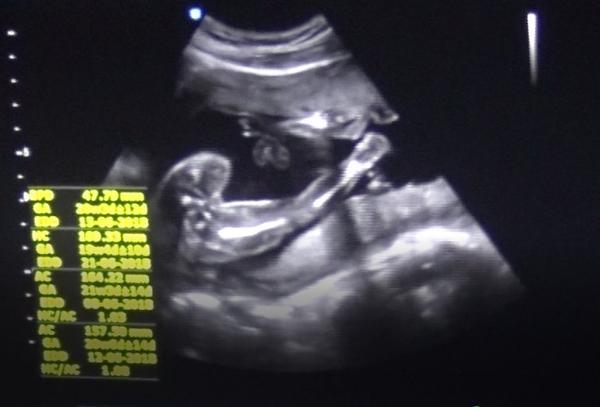

Asi spis chlapecek.

Maminky tak jste měli pravdu máme kluka 💙

@nikolaa123 řekla bych, že to jsou kulky 😁